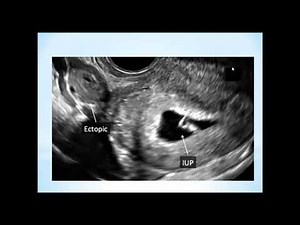

Pregnancy - Heterotopic

Pregnancy - Ectopic Pregnancy

Ultrasound - Ectopic Pregnancy